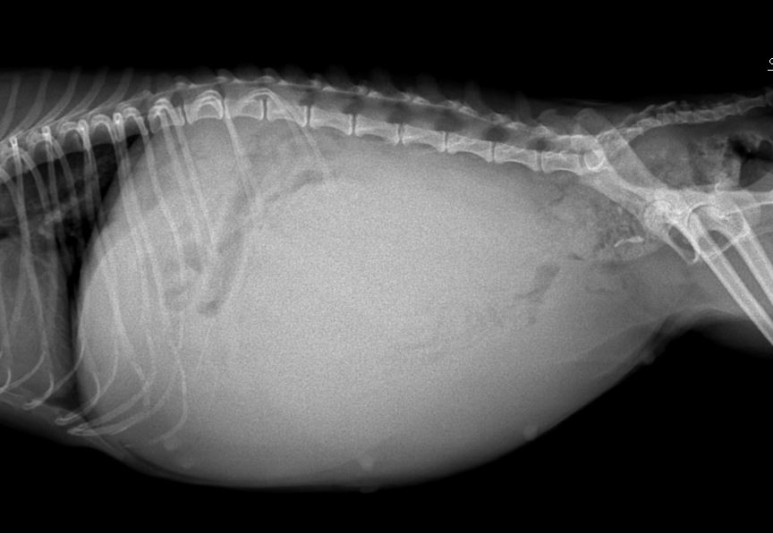

환자는 체중이 2.2킬로그램으로 몸집이 작고, 배가 상당히 부풀어 있었습니다.복부의 상태를 확인하기 위해 엑스레이를 촬영한 사진을 보도록 합시다.

복부가 많이 부풀어 올라와 있어요.뿌옇게 복강 내를 가득 메운 것이 보이고 팽창된 자궁이 복부를 가득 메운 형태입니다.

환자는 폐쇄형 자궁축농증으로 자궁내 삼출물에 의해 자궁이 파열되면 복막염, 패혈증을 유발할 위험이 매우 높은 상황이었기 때문에 응급수술에 들어갔습니다.아래의 환자를 보시면 아이의 작은 몸에 비해 매우 부풀어 오른 복부를 확인하실 수 있습니다.